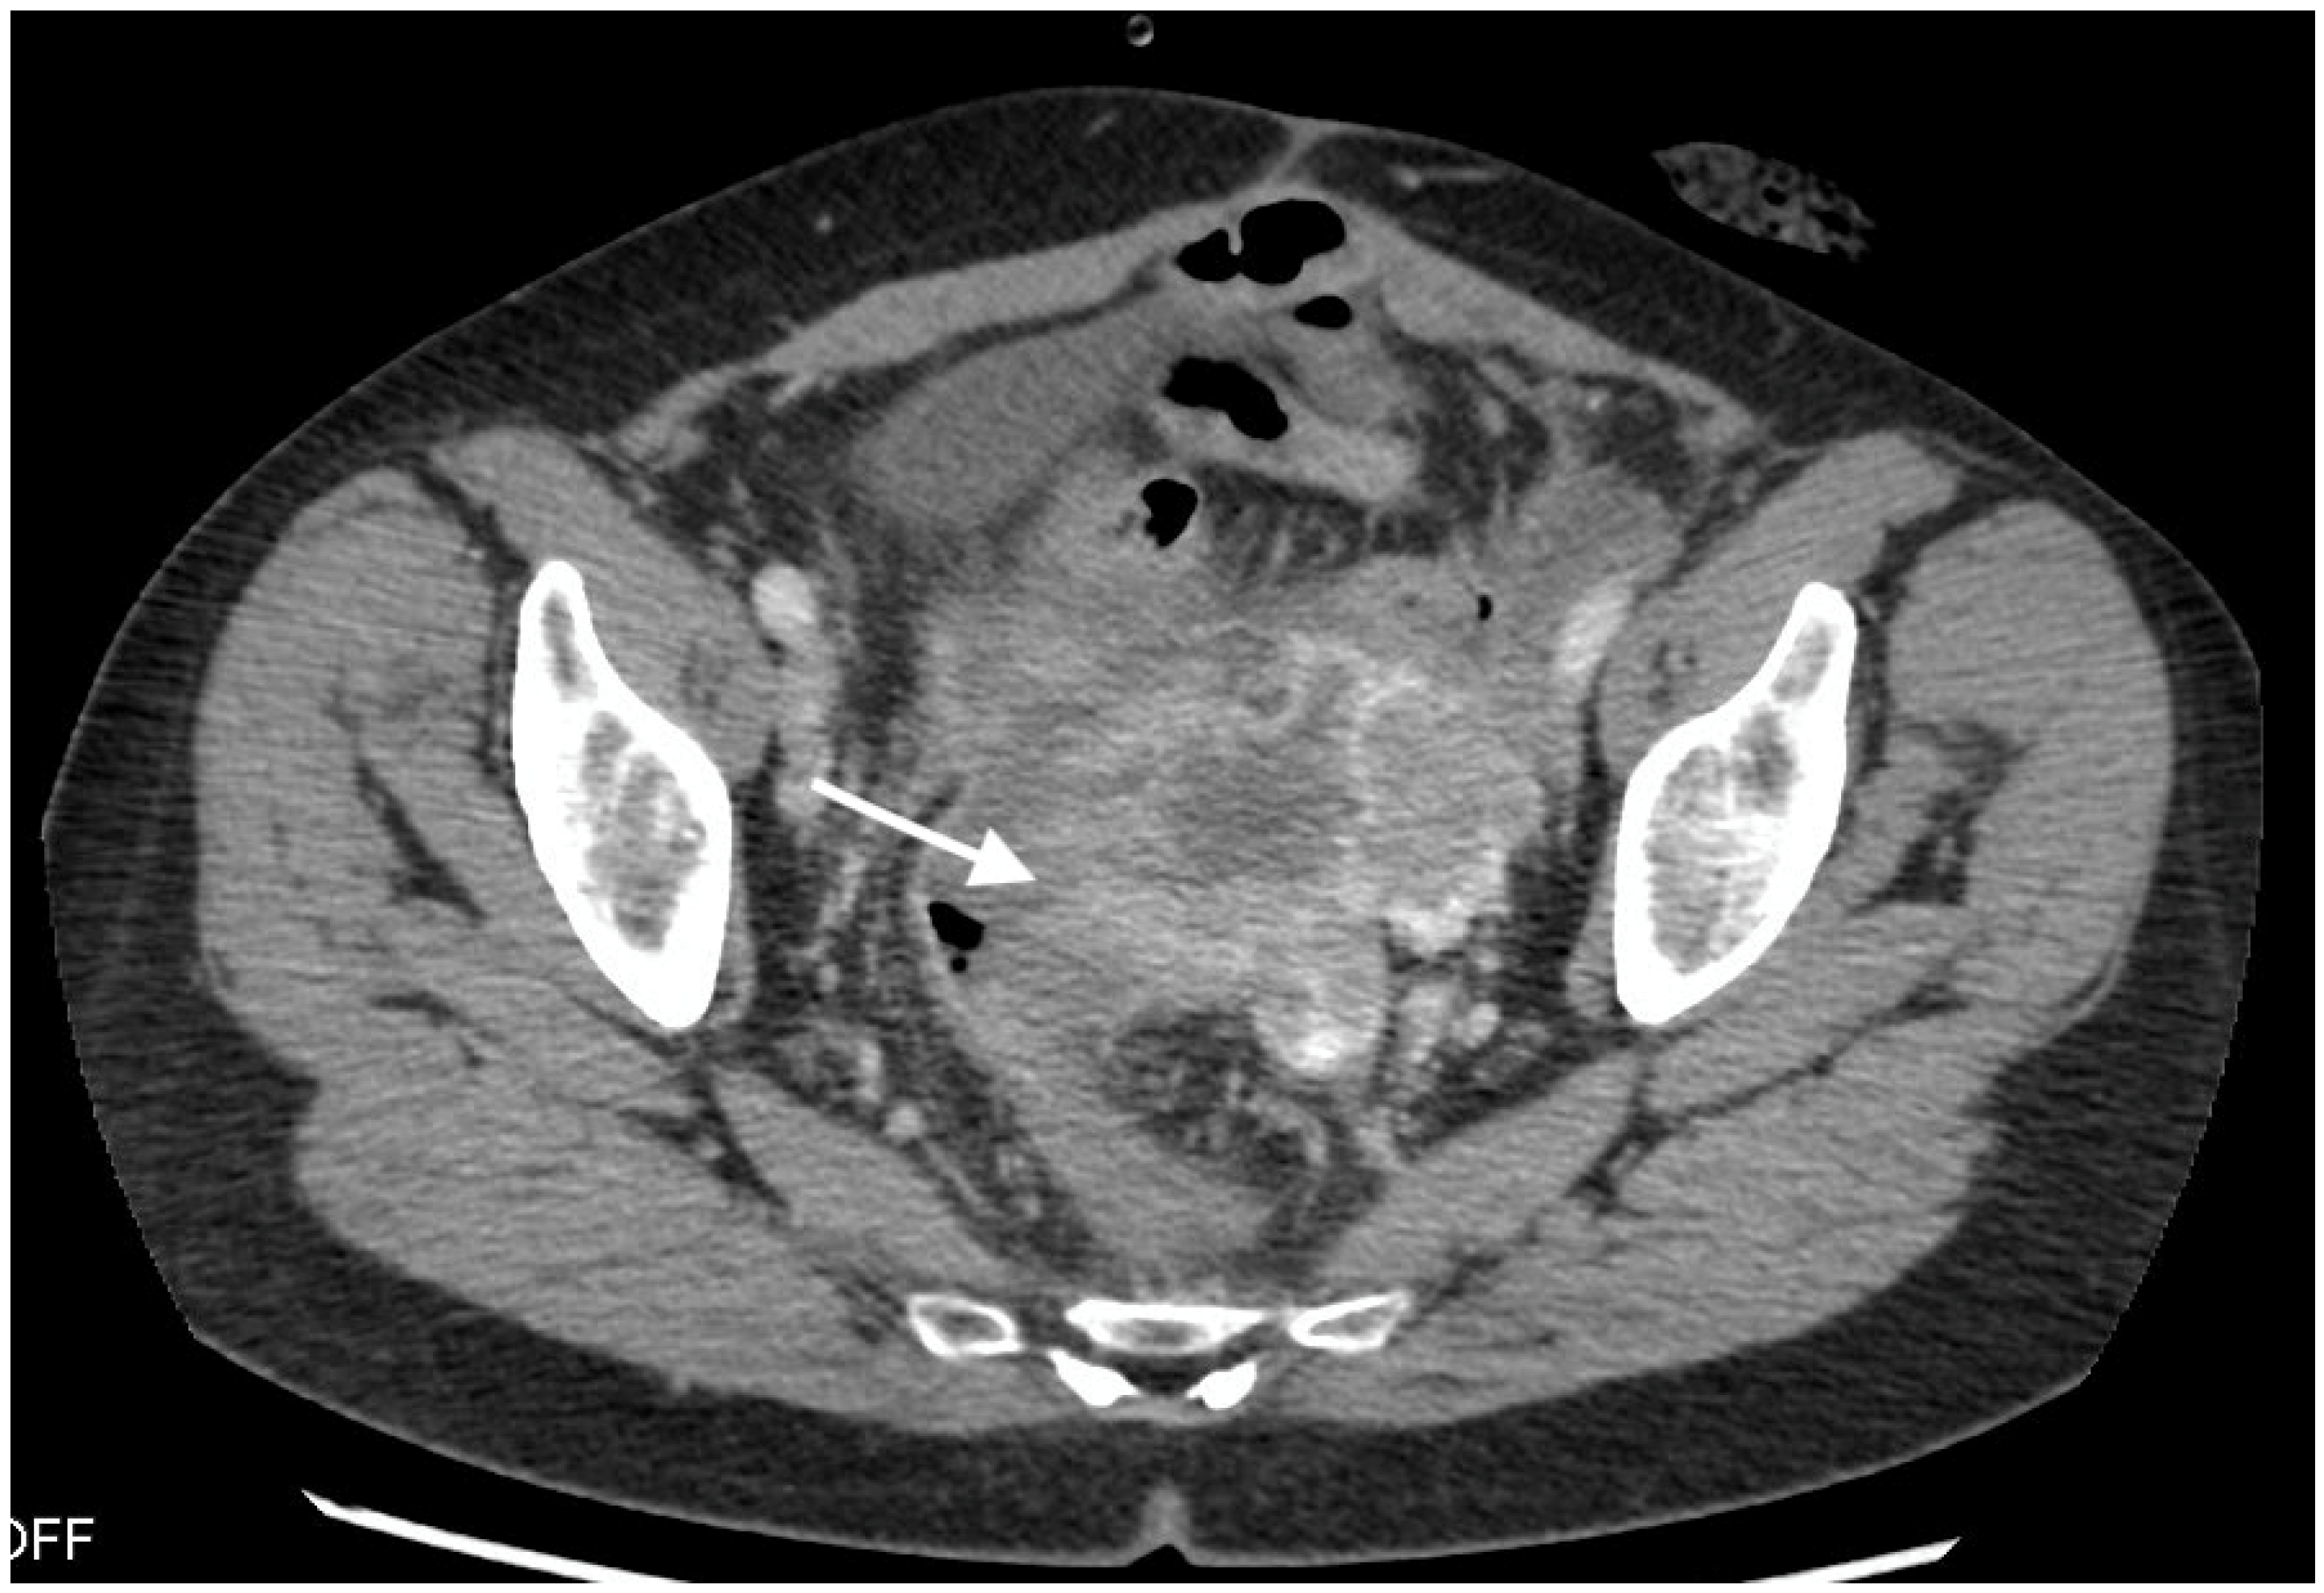

3.1. Imaging Findings